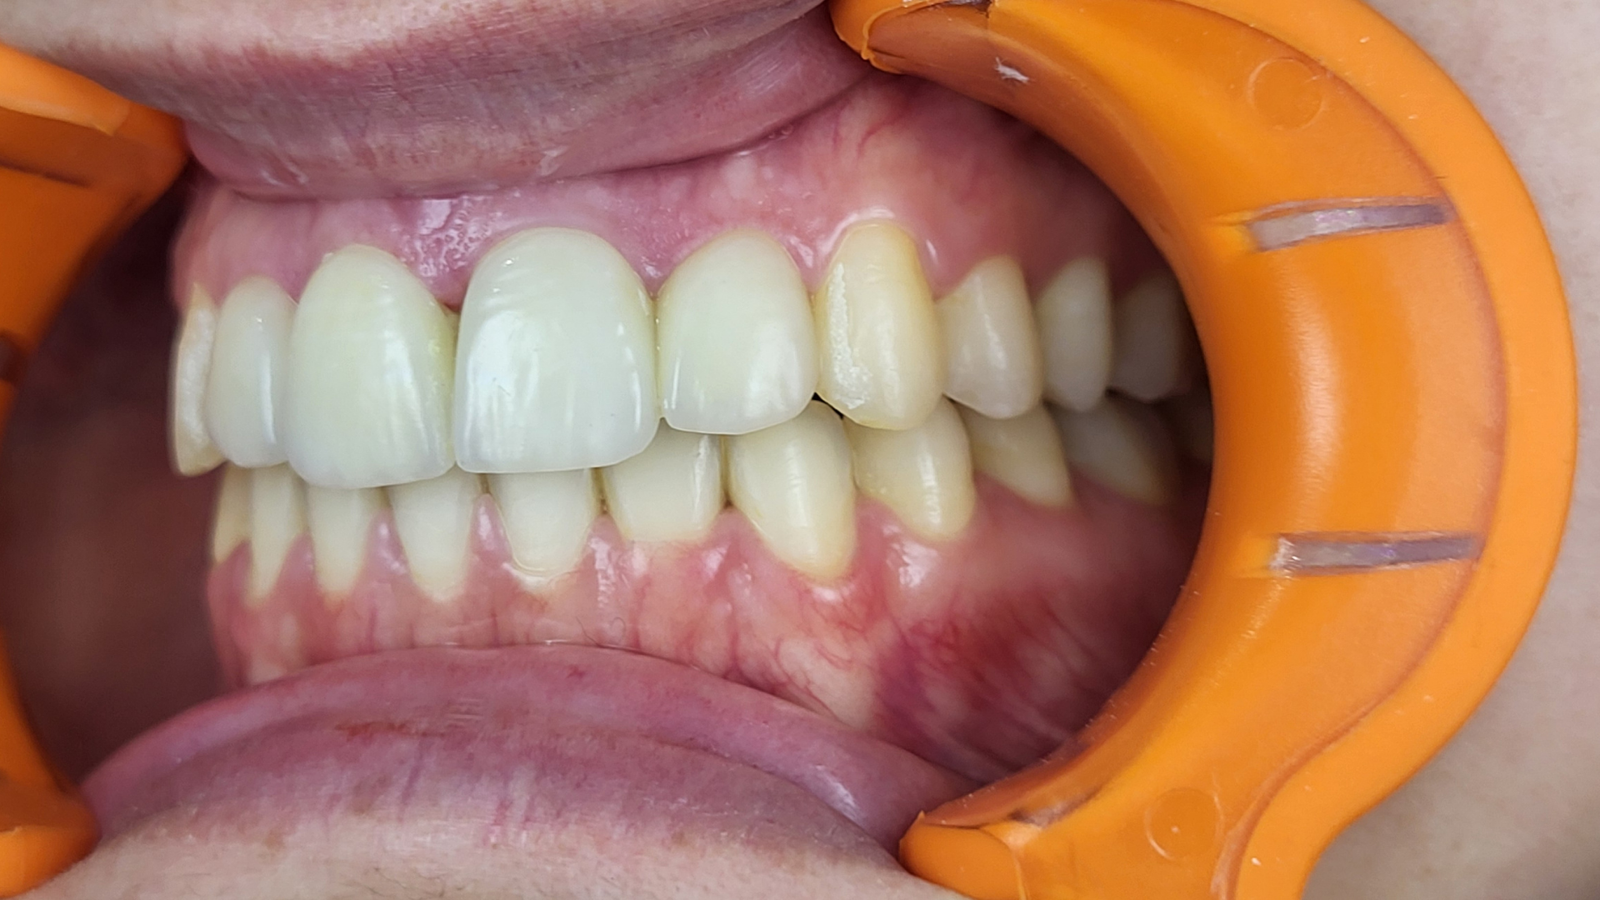

Réhabilitation complète avec mise en charge immédiate (4 implants bas / 6 implants haut)

Le patient se présente avec des dents qui bougent, en haut et en bas.

Nous avons commencé par la mâchoire inférieure avec 4 implants et une mise en charge immédiate.

Trois mois après, le haut a été fait avec le même principe avec 6 implants.

Cette fois-ci, il existait un déficit osseux, résolu par une technique d’expansion sans avoir recours à la greffe d’os.

Les prothèses réalisées sont vissées, ce qui permet de les enlever, les nettoyer une fois par an, ou résoudre n’importe quel problème.